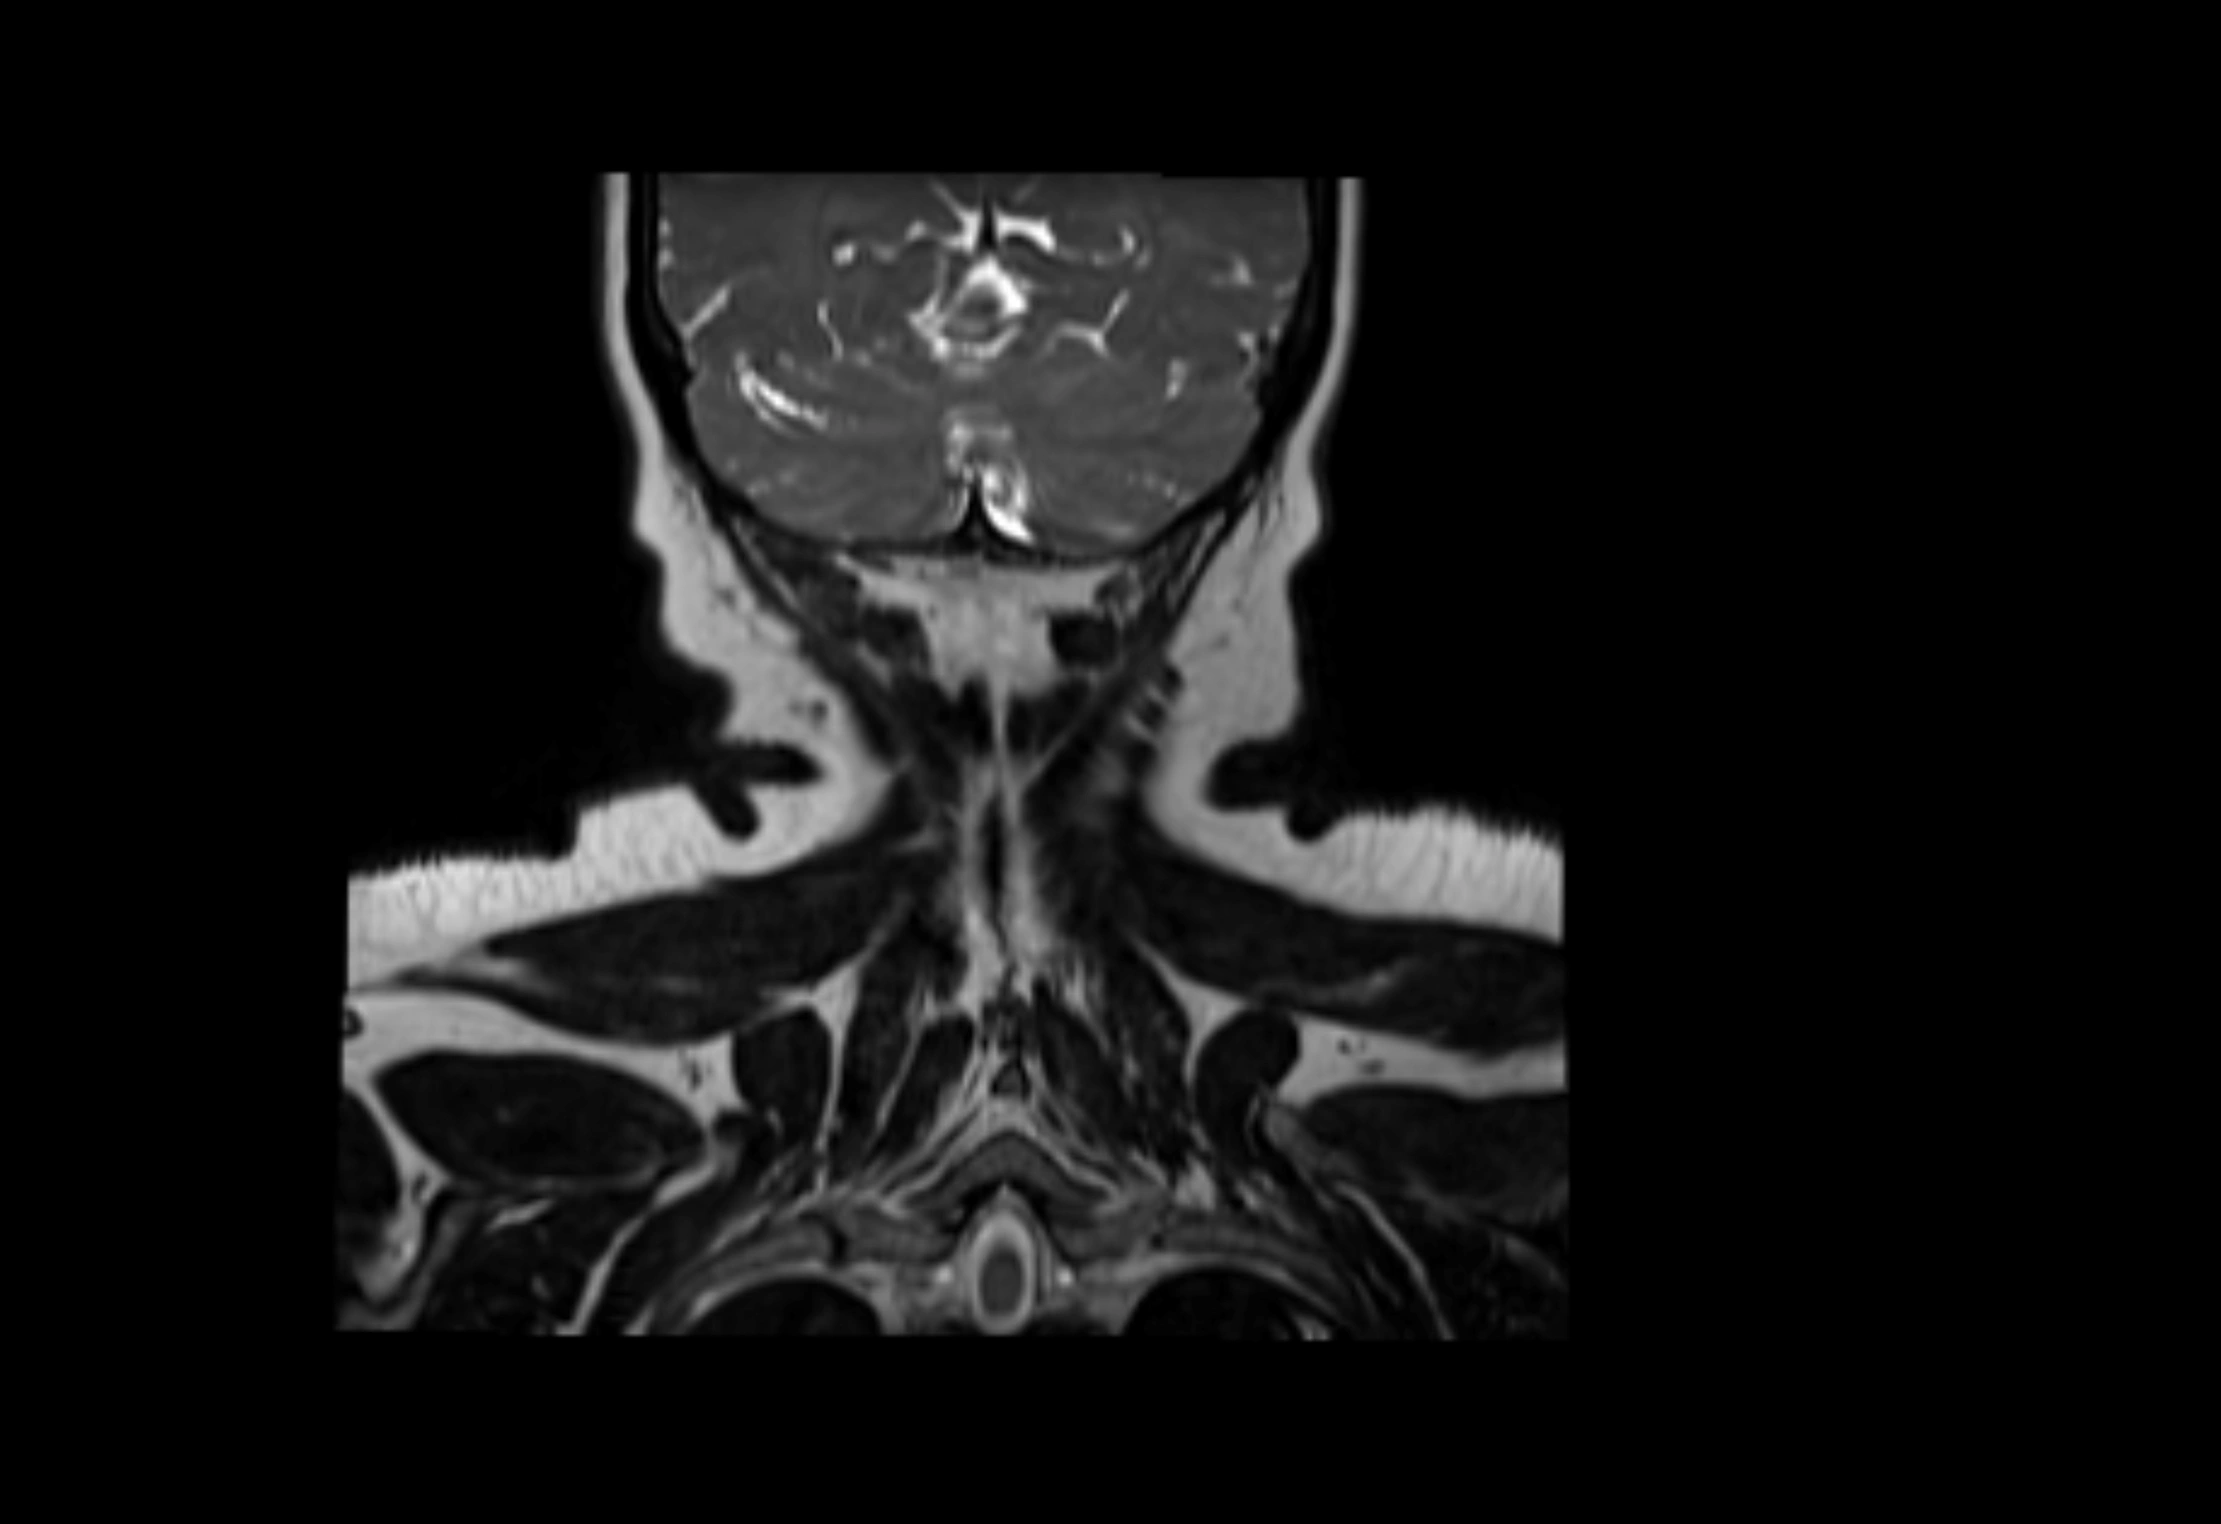

MRI Appearance

T1-weighted images:

• Normal accessory nodes appear as small, oval hypointense to intermediate signal structures within subcutaneous fat

• Surrounded by hyperintense fat, enhancing contrast for visualization

• Pathological nodes may appear enlarged or rounded, sometimes with cortical thickening

MRI images

image